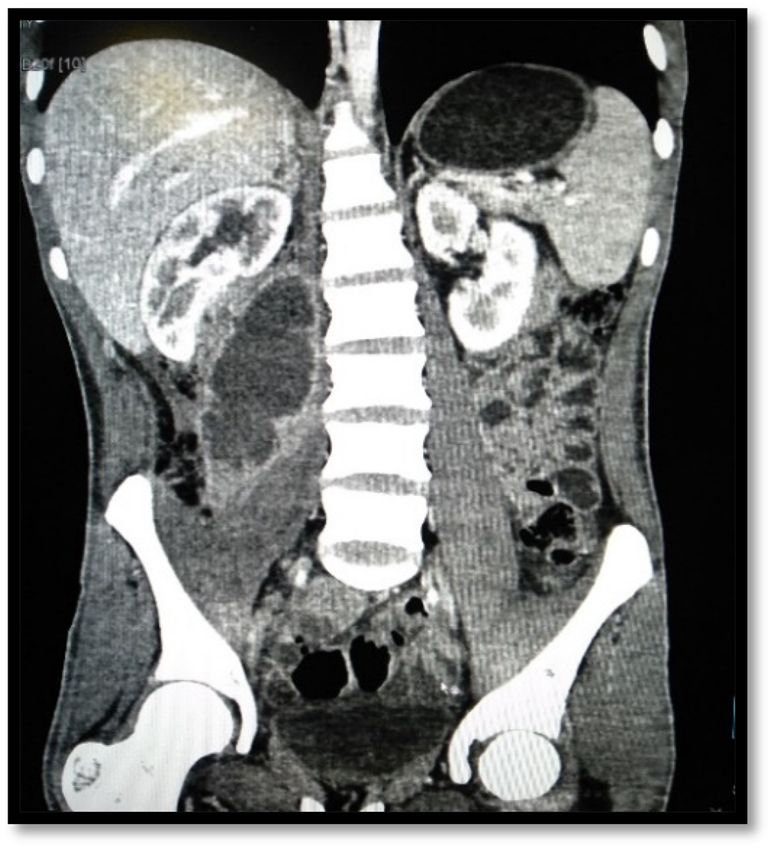

US was done in all cases of IPA, but was diagnostic in 27 (84.4%) patients (Figure 1). CT was done in 28 (87.5%) patients and MRI in 3 (9.4%) for further characterisation of abscess and underlying cause (Figure 2). Eighteen (56.3%) patients had primary IPAs without causal origin, and 14 (43.7%) had secondary IPAs (Table 2). The most common cause of secondary IPA was spinal tuberculosis 7 (21.9%). Right-sided unilateral involvement was the most common presentation in 16 (50%) cases with 12 (37.5%) cases involving left side and 4 (12.5%) cases having bilateral iliopsoas abscess. Multiple IPAs were found in 5 (15.6%). The estimated mean Volume of abscess on US was 114.1 ± 92.9 mL (range, 30–410 mL) (Table 2).

Coronal CT scan images of the abdomen and pelvis shows right sided iliopsoas abscess.